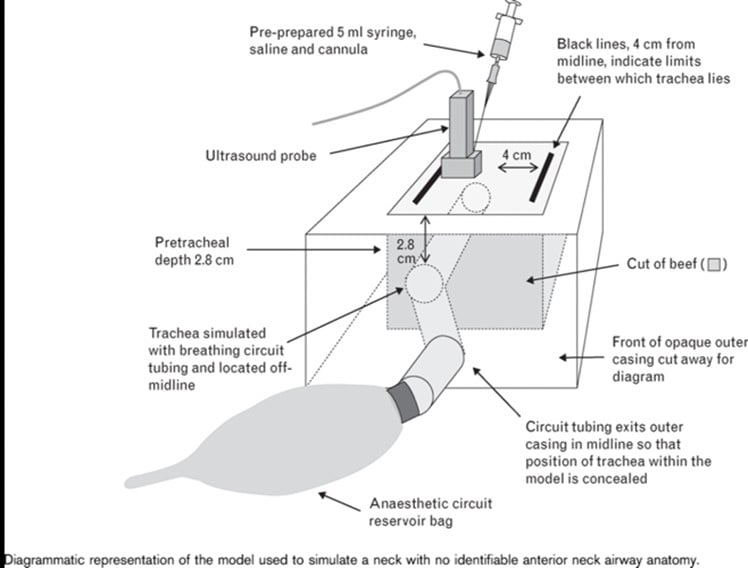

Figure 3. A porcine model for teaching ultrasound-guided cricothyrotomy

Figure 4. A combination plastic and meat-based model for teaching ultrasound-guided cricothyrotomy